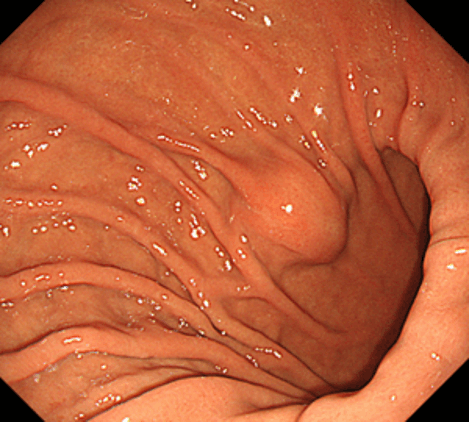

胃上皮下病変とは、胃の上皮(粘膜表層)の下の粘膜固有層(粘膜深層)や粘膜下層、固有筋層などに由来する腫瘤の総称です。以前は粘膜下層と固有筋層に局在する消化管間質腫瘍(GIST)、神経鞘腫、平滑筋腫、脂肪腫、迷入膵などを総称して粘膜下腫瘍(SMT)とすることが多かったのですが、近年は胃神経内分泌腫瘍などの、粘膜下層よりも浅層の粘膜固有層に主座を置く病変なども含めて、上皮下病変(SEL)とするのが一般的となりつつあります。本項では、従来のSMTに相当する病変について解説していきます。胃神経内分泌腫瘍については、別項をご参照ください。